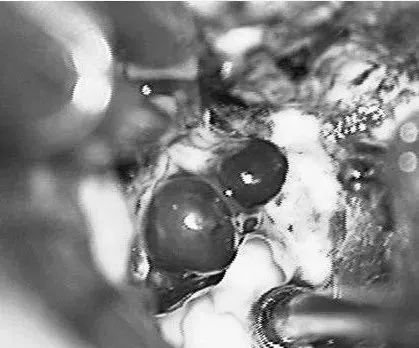

患者案例2:17岁男孩,表现为来自于右侧胼胝体压部AVM的脑室内出血(补充Spetzler-Martin分级4级:S1V1E1/A1B0C0),SplenA供血,SplenV和内侧AtrV引流右椎动脉造影。

手术步骤图解

(a)侧位(b)前后位].(c)他取侧卧位,右侧朝下,鼻朝下,中线取水平位以便靠重力牵拉右侧枕叶。窦汇开颅,显露SSS、TrvS、枕较、后纵裂和镰幕交界处。SplenA沿胼胝体压部上升,顺着它可达AVM(续)。